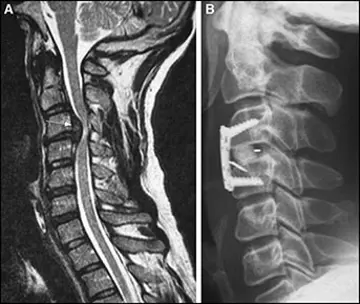

فتق دیسک گردن